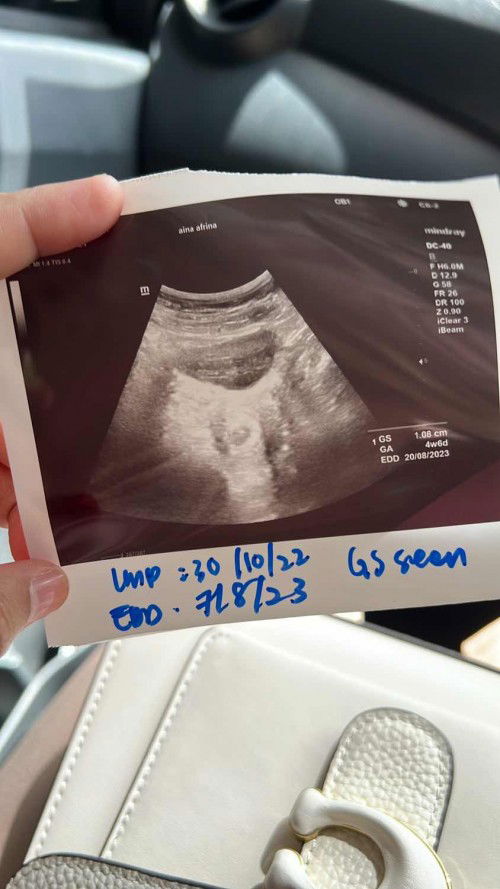

Early pregnancy scan

Hi mommies… Alhamdulillah after 2years ttc diizinkan oleh Allah swt rezeki zuriat.. kalau ikutkan 1day last period should be around 7w.. Tapi scan 17/12 haritu kandungan baru 4w6d nampak kantung n mcm biji kacang peas.. Huhu normal ke mommies2 ?? Lagi 3minggu repeat scan lagi..